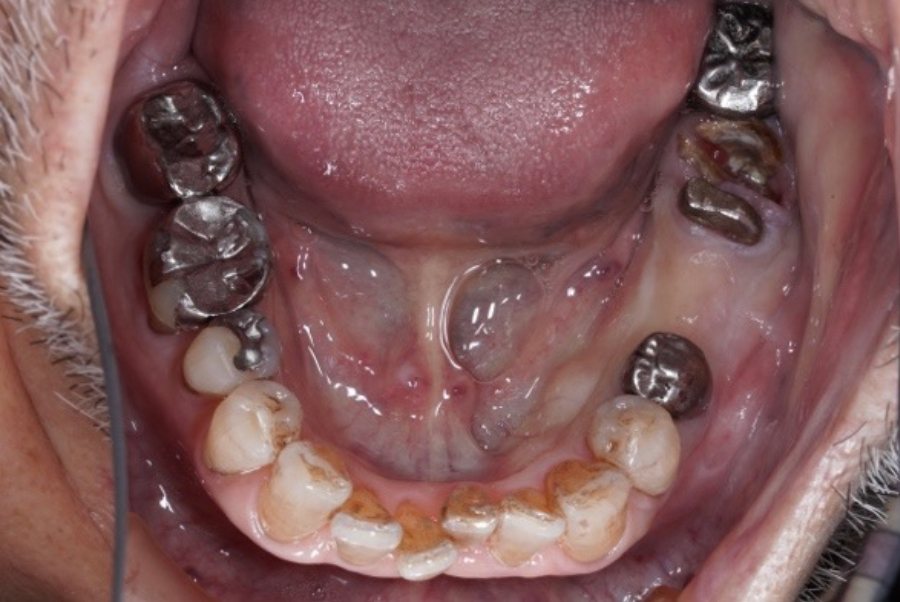

札幌駅前|

左下1本インプラント(6番)|

歯根破折・ブリッジ破損

からの回復症例

|80歳男性

- 治療内容

- CTによる精密検査を行い、骨量・骨質・神経位置などを詳細に評価した上で治療計画を立案しました。

抜歯後、左下6番にインプラントを1本埋入し、周囲の歯に負担をかけない形で機能回復を行いました。